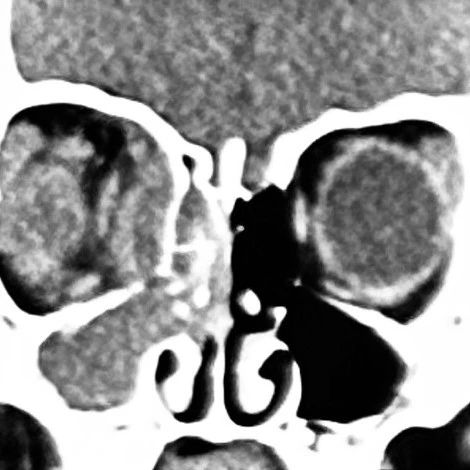

患儿的CT影像

根据患儿的CT表现,符合鼻窦炎的眶并发症,属于眼科和耳鼻喉科的急危重症。药剂科认为,目前患儿已经接受了经验性广谱抗生素的治疗,眼部红肿没有明显好转,病灶持续扩大,患儿仍有发热、食欲不振等严重感染的全身表现,考虑药物治疗效果差,目前脓肿已形成,需积极进行手术引流。

耳鼻喉科闫燕主任高度重视患儿病情,组织全科进行了病例讨论。考虑到患儿是3岁女童,眼部切口进行眶内脓肿引流对于患儿将来的面容存在影响,且术后眼部换药患儿难以配合,CT所见患儿炎症集中在眼眶内壁周围,可以尝试经鼻进行手术。马芙蓉教授阅片后发现,患儿的眶内下角存在一个非常小的骨质不连续区域,可能是炎症从鼻窦向眼眶感染的通道,也是经鼻进行引流手术的关键突破口。